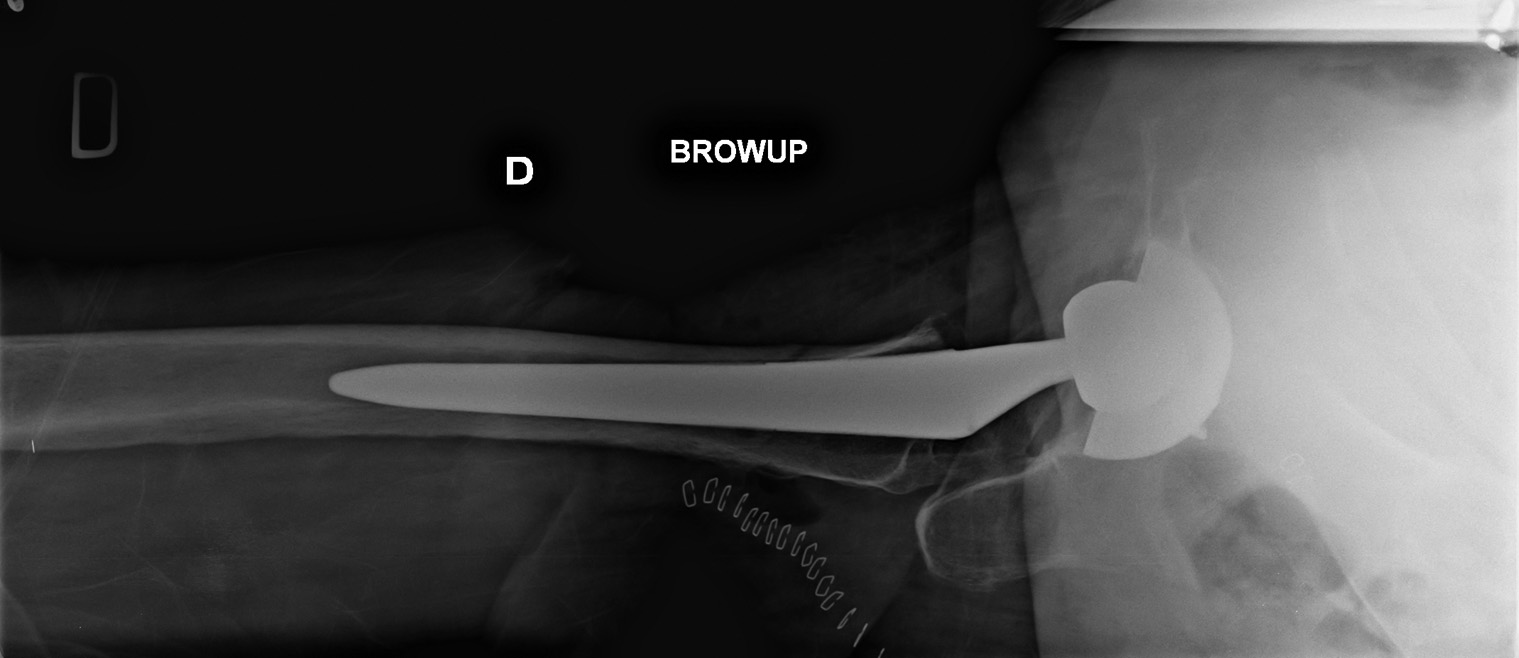

Postoperative control of a total hip arthroplasty.

Right total hip replacement. The femoral component is uncemented and has a press-fit fixation.

The acetabular component is held by press-fit and one screw in the pelvis.